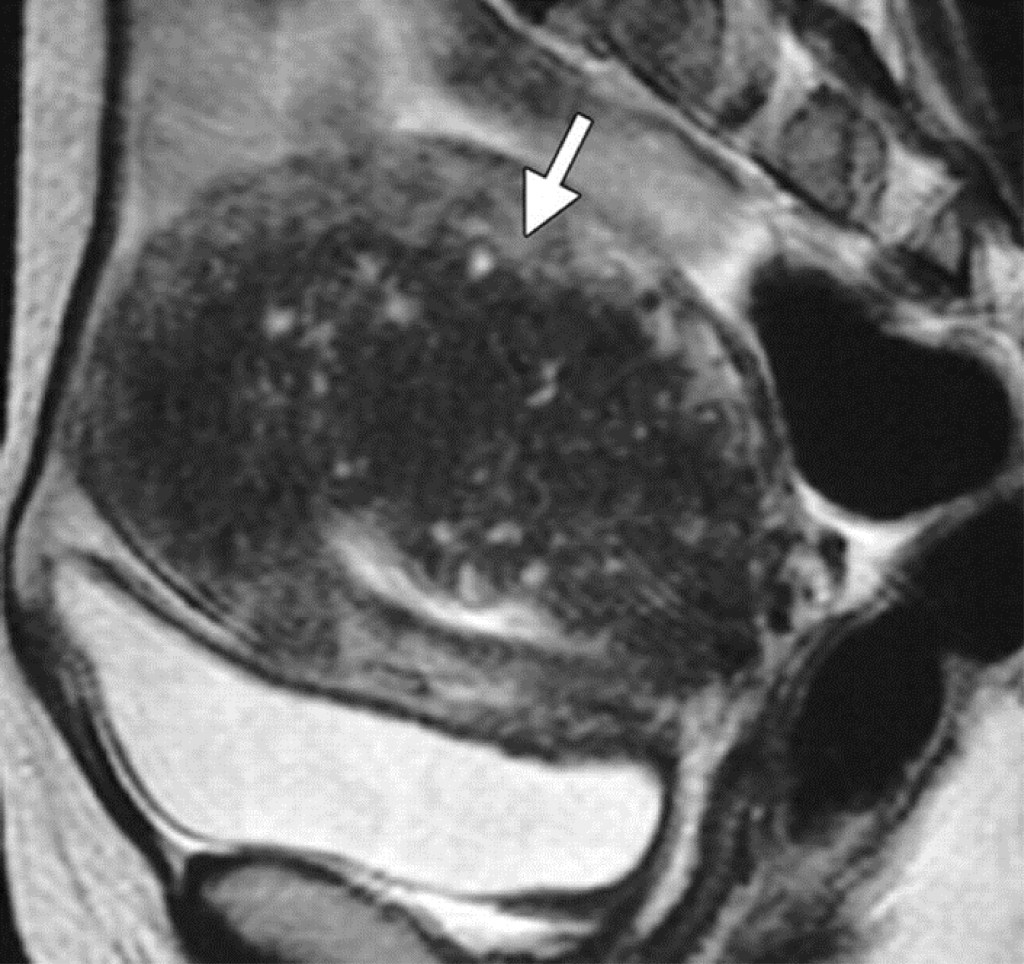

Magnetic resonance imaging (MRI). An MRI uses magnetic fields, not x-rays, to produce detailed images of the body. A special dye called a contrast medium is given into patient’s vein before the scan to create a clearer picture. MRIs create more detailed pictures than CT scans and are the preferred way to diagnose a brain tumour. The MRI may be of the brain, spinal cord, or both, depending on the type of tumour suspected and the likelihood that it will spread in the brain and spinal cord. There are different types of MRI, doctor will helps determine which type of MRI to use.